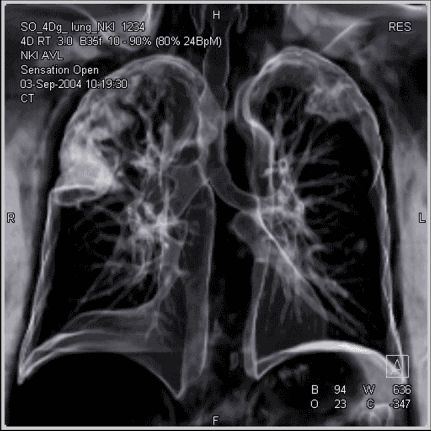

这是我们的肺部正在呼吸